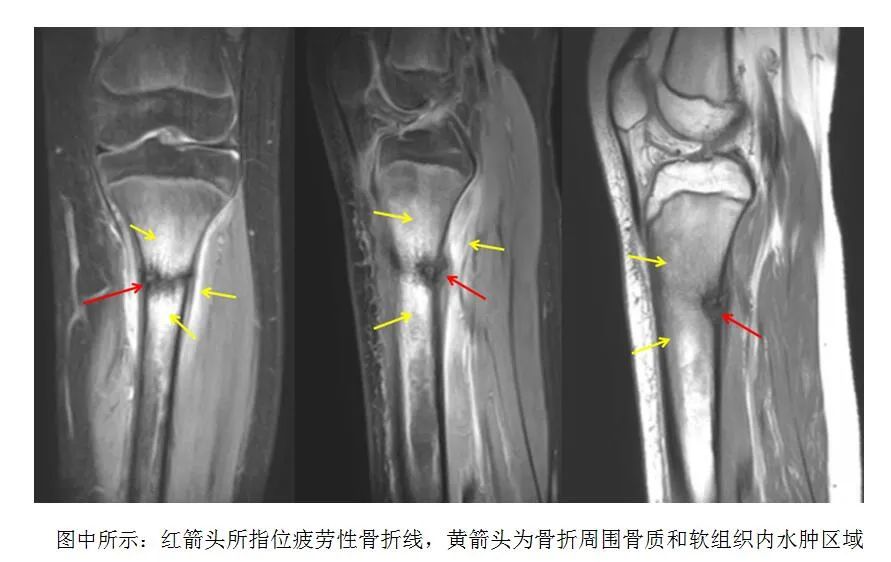

前不久,一名女孩因“右膝關(guān)節(jié)疼痛”到漯河市骨科醫(yī)院(漯河醫(yī)專二附院)就診,經(jīng)過MRI檢查發(fā)現(xiàn),她右側(cè)脛骨上段大片骨髓水腫,并伴有局部細微骨折線,最終被診斷為疲勞性骨折。

在出現(xiàn)癥狀的初期如果我們?nèi)メt(yī)院拍攝X線片或CT,可能會無明顯異常發(fā)現(xiàn),往往持續(xù)發(fā)展到較嚴重時期才可以在X線檢查中發(fā)現(xiàn)異常。因此,早期當臨床疑有疲勞骨折,而X線片或CT檢查無明顯異常時,可考慮采用磁共振(MRI)檢查,發(fā)病早期即可發(fā)現(xiàn)骨折區(qū)域水腫信號以及骨折線出現(xiàn)。